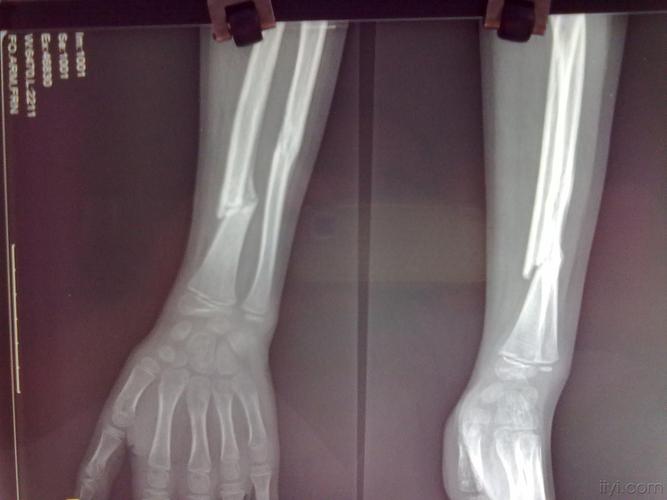

左手尺桡骨骨折图片

左手尺桡骨骨折图片,左尺桡骨骨折图片

尺桡骨双骨折

儿童尺桡骨远端骨折

左尺桡骨骨折图片

尺桡骨骨折图片